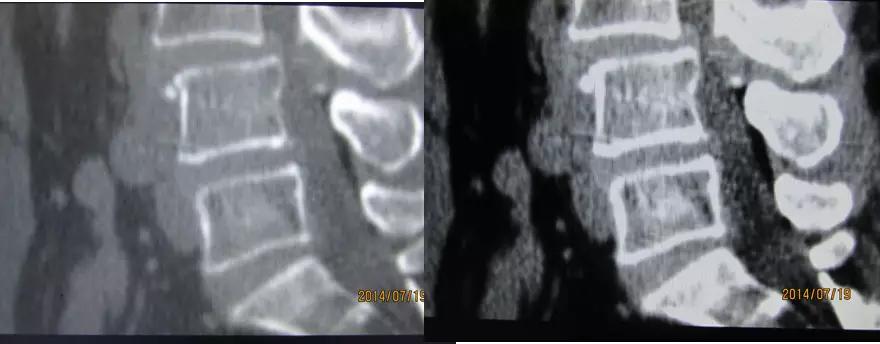

二、腰 椎

L1-2至L4-5的椎间盘形态大致相似,呈肾形,后缘年轻人稍凹,凹陷部与后纵韧带走行一致,随着年龄的增长,后缘可变得平直。

正常L5-S1椎间盘的后缘较平直,并可轻微膨出。

椎间盘由髓核和纤维环组成,略高于软组织密度影,CT值为80~120HU,CT不能区分髓核和纤维环。

黄韧带厚约2~4mm,超过5mm为肥厚。

正常小关节面光滑、完整,关节间隙为2~4mm。

L1-L5、L5-S1正常椎间盘

椎基静脉影

椎间孔前为椎体,后为椎小关节,上下为椎弓根,内与侧隐窝相连,有脊神经根通过。

侧隐窝:向下外续于椎间孔,有脊神经经过:前壁为椎体后外缘;后壁为上关节突前面与黄韧带;外界为椎弓根。

正常前后径为3-5mm,<3mm侧隐窝狭窄>5mm,肯定不狭窄。